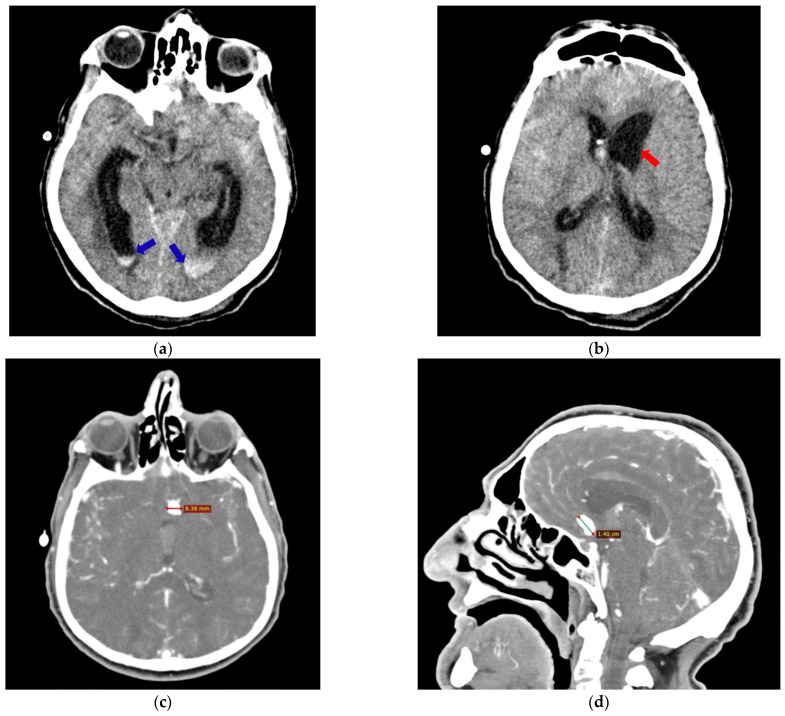

Methods: We investigated the anatomical variants of the CW associated with the occurrence and rupture of AcoA aneurysms by performing comparative analyses, in the same patients, of postmortem autopsy data with antemortem computed tomography-angiography (CTA) results obtained in the first 48 h after the onset of subarachnoid hemorrhage. Our retrospective observational study identified the anatomical variants of the CW at autopsy in 16 deceased adult Romanian patients with AcoA aneurysms over a 12-year period (2010-2022).

Results: The autopsy findings revealed that the AcoA ruptured aneurysms had a mean external diameter of 9.50 mm, and 71.4% of them presented three or four anatomical variants inside the same CW. The initial antemortem CTA examination correctly located the AcoA aneurysms in all cases (100%), and an anatomical variant of the CW was only noted in 18.75% of patients. The final postmortem re-analyzed the same CTA images identified in all cases (100%), focusing on both the AcoA aneurysm and all anatomical variants of the CW found during the autopsies.